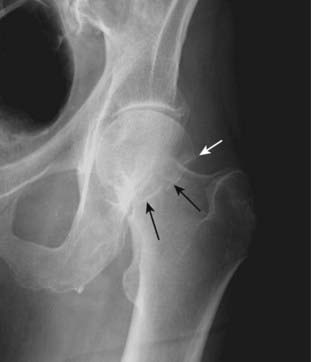

Figure 22-11 Avulsion fractures, ASIS and lesser trochanter.

Avulsion fractures are common fractures in which the avulsed fragment is pulled from its parent bone by contraction of a tendon or ligament. Although avulsion fractures can occur at any age, they are particularly common in younger individuals who engage in athletic endeavors. There is an avulsion of the anterior superior iliac spine (ASIS) (solid white arrow), which is the site of the insertion of the sartorius muscle. There is also an avulsion of a portion of the lesser trochanter, on which the iliopsoas muscle inserts (dotted white arrow). The patient had participated in track and field events a week prior to this radiograph.